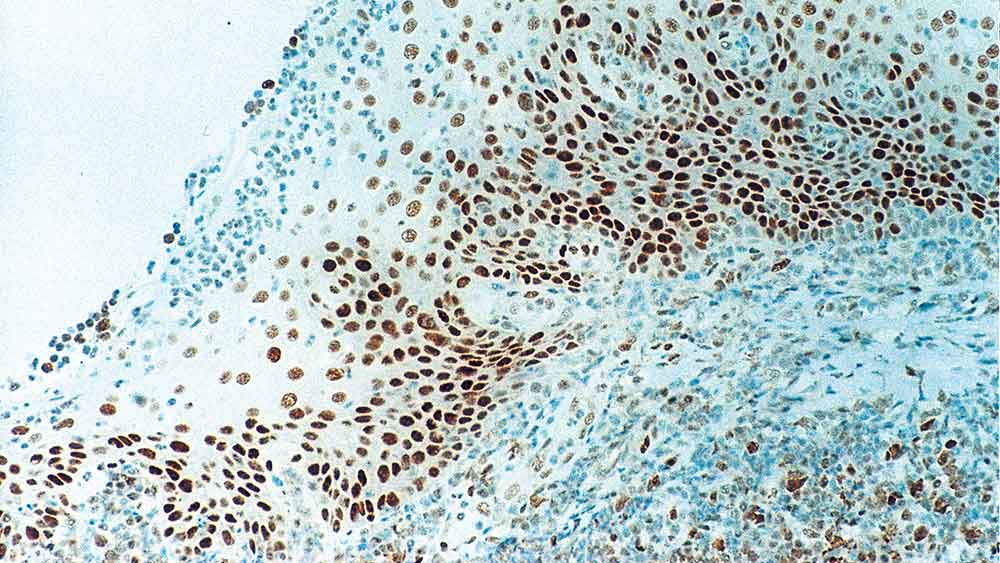

Human tonsil: immunohistochemical staining for Retinoblastoma Gene Protein. Note intense nuclear staining of epithelial cells. Retinoblastoma Gene Protein: clone 13A10

Das Retinoblastom (Rb) ist ein seltener Tumor der Netzhaut, der mit Mutationen des Chromosoms 13 assoziiert wird. Das durch das Rb-Tumorsuppressor-Gen codierte nukleäre Phosphoprotein ist in zahlreichen Zellen vorhanden und reguliert, möglicherweise indirekt, das Zellwachstum durch Aktivierung des Transkriptionsfaktors ATF-2.

Die Aktivierung von ATF-2 initiiert die Expression von TGF-β2, was wiederum die Transkription von Genen hemmt, die das Zellwachstum beeinflussen. Die bilaterale Mutation des Rb-Gens kann bei der Entwicklung einer Reihe bösartiger Tumoren potenziell eine Rolle spielen.

NCL-RB-358 wurde für die N-terminale Region des Rb-Gen-Proteins entwickelt.